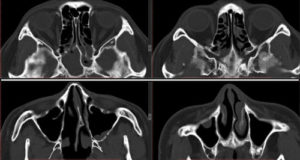

- информативнее других методов обнаруживают сфеноидит компьютерная или магнитно-резонансная томография;

- при недоступности КТ и МРТ выполняется рентгенологическая диагностика;

КТ — исследование пазухи с помощью рентгеновского излучения. КТ позволяет выявить аномалии синуса, степень поражения слизистой. При исследовании с помощью КТ определяется уровень гноя в пазухе.

Ещё более информативным методом диагностики является МРТ — она выявляет послойные поражения, которые могут быть не замечены на КТ.

Единственными методами, которые наверняка могут определить сфеноидит, являются компьютерная томография (КТ) или магнитно-резонансная томография (МРТ) –